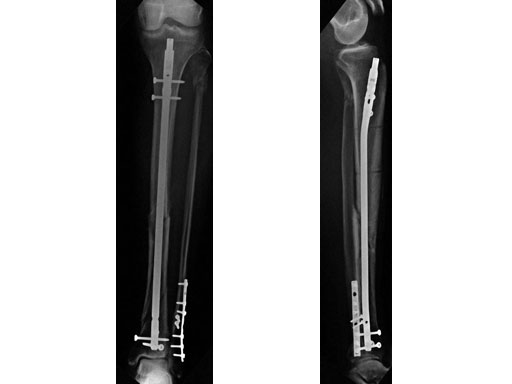

48-year-old male. Tibia shaft fracture with fibula fracture.

Case provided by Hermann Bail, Berlin, DE